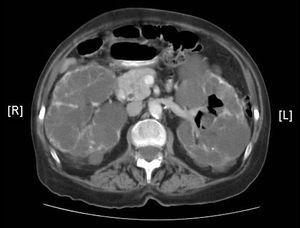

Se presenta el caso de una mujer de 70 años diagnosticada de poliquistosis renal del adulto, que inició hemodiálisis periódica cuatro meses antes. Ante la persistencia de síndrome constitucional, resistencia a eritropoyetina, anemia, etc se consideró necesario ingreso hospitalario. En la anamnesis, la paciente refiere expulsión de aire tras la micción, sin más síntomas ni signos. Se realiza urinocultivo, cultivándose E. Coli. En Tac abdominal se observa la presencia de gas en vejiga y sistema colector urinario izquierdo (lo cual es francamente inusual) (fig.1). Instaurado tratamiento con Ciprofloxacino durante 12 días, y sondaje uretral, se consigue remisión clínica y radiológica completa con negativización del cultivo de orina.

Figura 1.